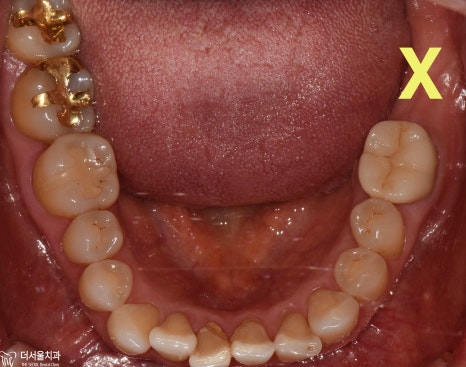

겉으로 보면

아무런 문제가 없어 보이는데

파노라마 엑스레이선 그렇지 않았습니다.

치조골 흡수로

잇몸뼈가 녹아내렸는데

왼쪽 어금니가 ‘다소’ 심각한 상태였습니다.